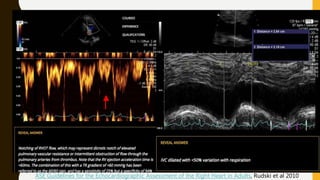

ECHO

ASE Guidelines for the Echocardiographic Assessment of the Right Heart in Adults, Rudski et al 2010

• Signs of RV pressure overload, defined as 1 or more of the following

signs:

– Right sided cardiac thrombus

– RV diastolic dimension on parasternal view of >30mm or a ratio of

RV to left ventricle of >1

– Systolic flattening of the interventricular septum

– Pulmonary valve acceleration time <90ms or tricuspid regurgitation

pressure gradient >30mmHg in absence of RV hypertrophy

– Tricuspid annular plane systolic excursion(TAPSE) <16 mm